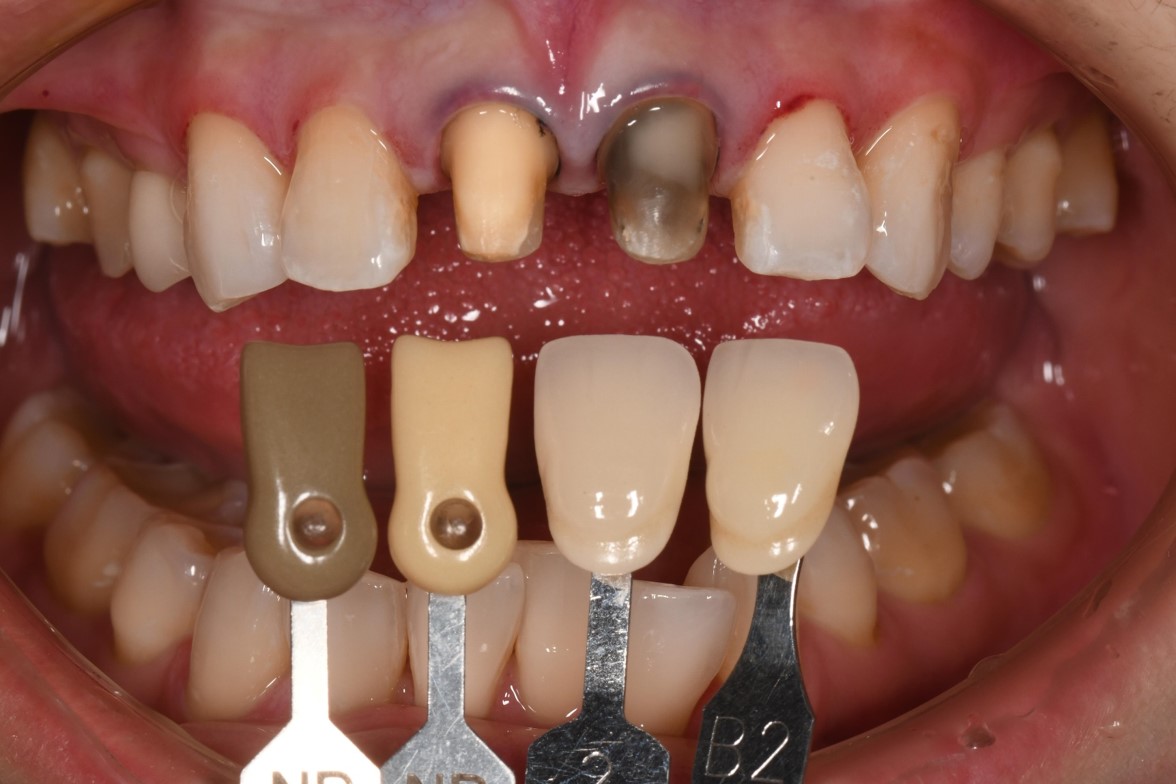

支柱牙與鄰牙照相比色

居家美白4週後,前進5色階